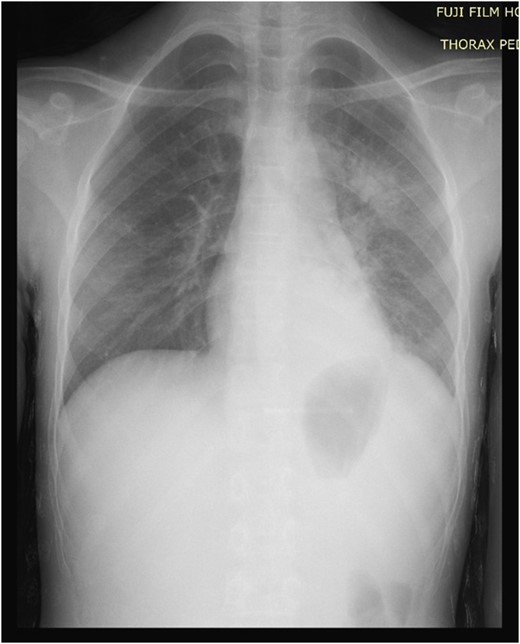

A 13-year-old female child was presented to the pediatric emergency unit with a painful swelling of the posterior left chest wall during the last 3 months. The patient was febrile without weight loss. She had a history of cutaneous mycosis for 2 years. The physical examination revealed a child in good general condition, febrile (axillary temperature was 38.2°C) and a painful swelling of the left posterior chest wall of ~6 × 4 cm2 (Fig. 1). The laboratory studies found a hemoglobin and hematocrit level of 10.5 g/dL and 34.4%, respectively, and a white blood cell count (WBC) of 15.210/μL with 80% neutrophils. Inflammatory indices such as erythrocyte sedimentation rate and C-reactive protein were greatly increased, with a level of 50 mm/h and 111 mg/L, respectively. The chest and the abdominal radiographs were found to be normal (Fig 2). The ultrasound showed an echogenic collection of the posterior chest wall of ~5 cm × 5 cm. A computed tomography (CT) scan of the chest with intravenous (IV) contrast showed a 6-3-5 cm pus collection of the posterior costovertebral region consistent with an osteomyelitis of the 10th, 11th, 12th ribs and soft tissue collection (Fig. 3). The abscess was incised and drained. A rib biopsy and a cytological examination of the pus were performed. Postoperatively the abscess was drained by a chest tube for two days before being removed. Postoperative antibiotic therapy with ceftriaxone, gentamicin and metronidazole was initiated. The pus culture was negative. Mantoux test and HIV test were negative. The histological examination of the rib biopsy disclosed a diagnosis of acute non-specific rib osteomyelitis. The patient was discharged after 2 weeks from hospital and the injection antibiotics were switched to oral administration (amoxicillin-acid clavulanic 80 mg/kg/day) for 6 supplementary weeks. The patient remains asymptomatic 6 months postoperatively.

Physical examination: a swelling of the left posterior chest wall of ~6 × 4 cm2.